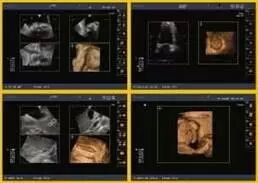

实时三维成像(4D)

不断创新的容积成像技术,结合了海量信息化的交响平台,全新的容积处理方式,增强容积图像的细节显示,提高图像真实感,加强临床诊断信心。